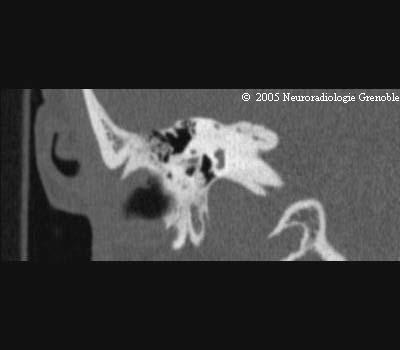

Radioanatomie TDM du rocher normal

Trou déchiré postérieur

Canal semi circulaire externe

Canal semi-circulaire supérieur

Vestibule

Antre